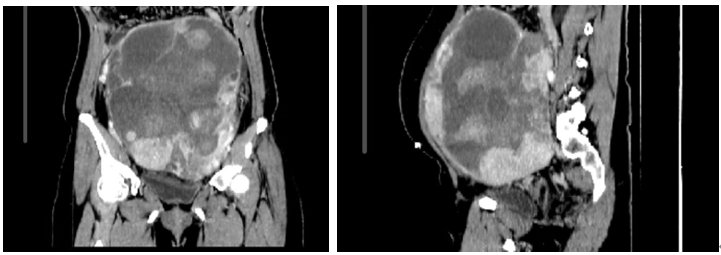

2017年7月7日腹部CT

2019-07-07腹部CT:直肠癌术后,吻合口未见异常。双侧附件区肿块,符合转移,右附件肿块可疑侵犯子宫体。肝、双肺转移瘤。脾缺失,右肾积水。

2019-2-2出现下体出血,05-15、6-6为缓解盆腔胀痛不适行CT行盆腔肿瘤穿刺活检术+微波消融术+盆腔穿刺置管引流术,病理示:盆腔肿物为肠癌转移性腺癌。查体:LN-,腹软,下腹至耻骨上区膨隆,触及巨大肿物,20*15cm,质硬,固定见皮肤引流管;肛查。